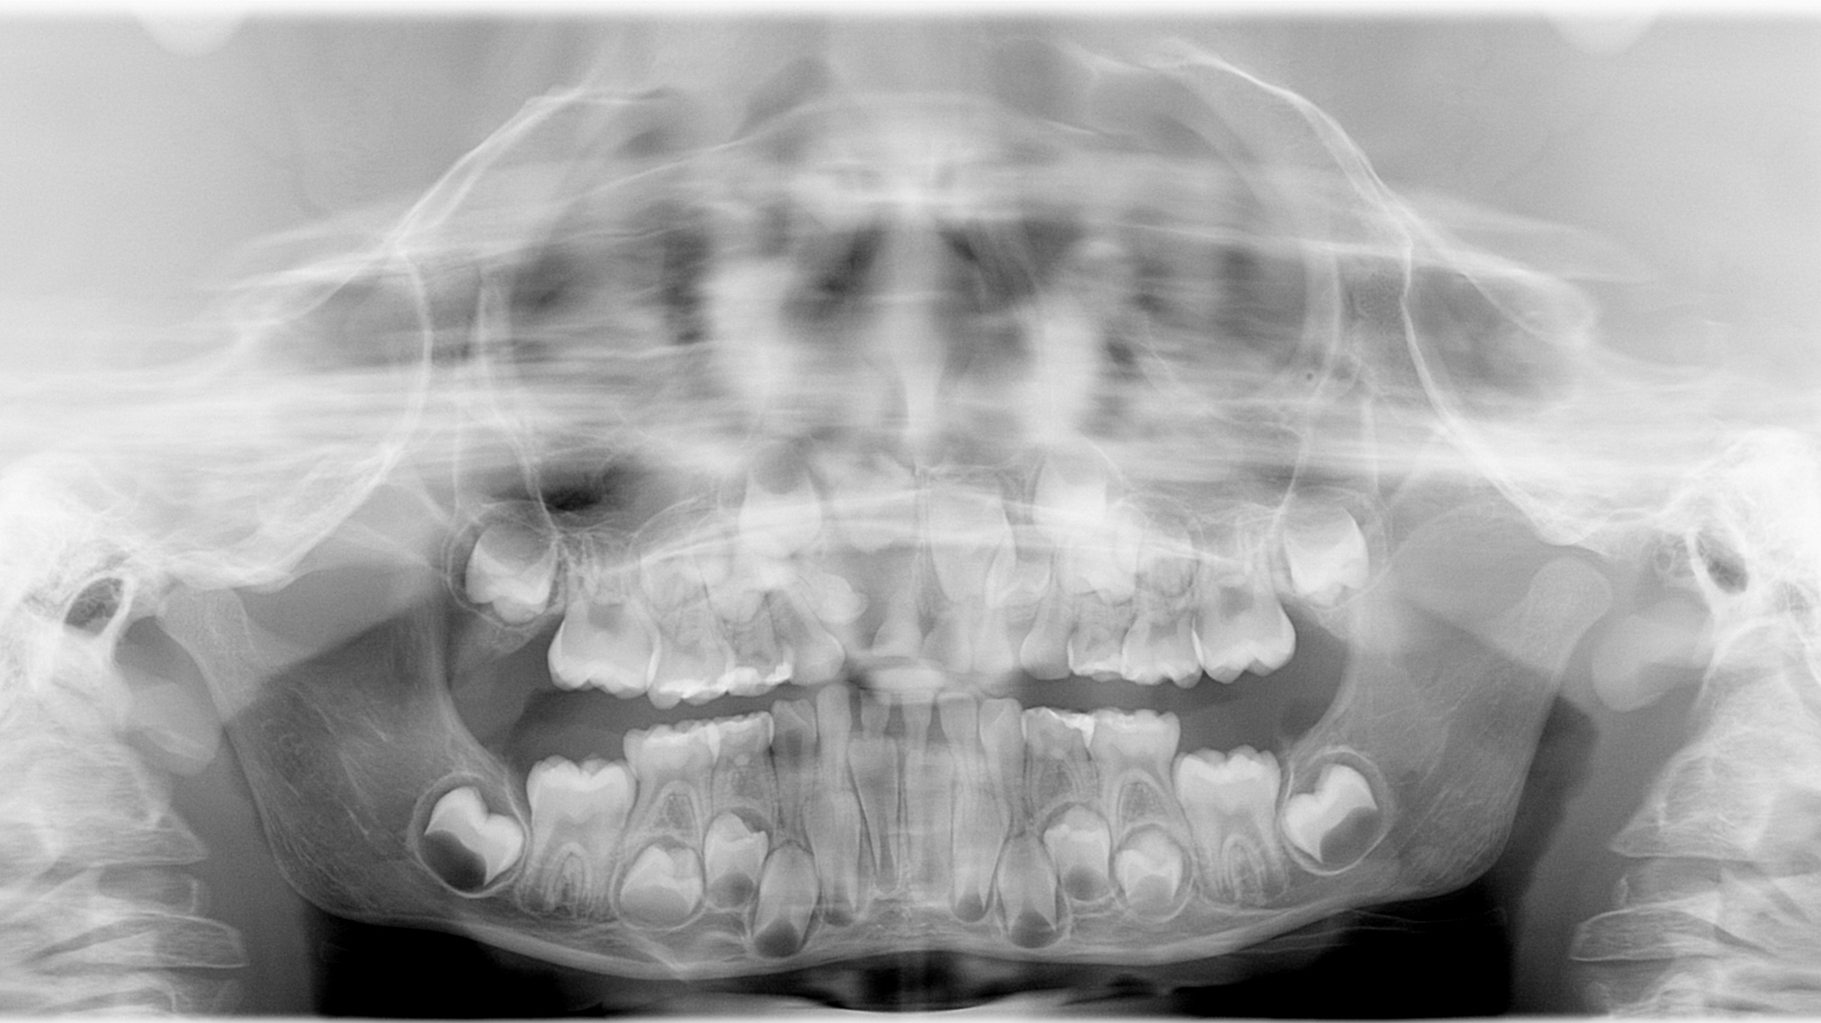

A healthy 7-year-old male presents for his new-patient exam. A radiolucency was noted in the no. 7 area on the panoramic radiograph; subsequent occlusals were referred to for a better view where the lesion appeared to focalize around the coronal portion of no. 7. Furthermore, there was an ill-defined radiopacity within the osseous tissue, under the area where primary tooth D would be located. The area was not tender to palpation nor was there any expansion noted in the vestibular area. Mom reported that the patient had trauma to the area a few years back while playing.

The most common form of pericoronal radiolucencies are dentigerous cysts (DCs).1 DCs are “caused by fluid accumulation between the enamel surface and the reduced enamel epithelium, resulting in a cyst in which the crown is located within the lumen and root(s) outside;”2 the underlying reasoning is unknown. The most common teeth affected are mandibular third molars, maxillary canines, mandibular premolars, and the maxillary canines.1,2 It is not uncommon for a DC to displace the unerupted tooth and often any adjacent teeth. Typically, DCs are painless and slow growing; however, pain will manifest if swelling and inflammation are present.

In this particular case, the patient was referred to an oral surgeon, who removed a root fragment of what was assumed to be tooth D as well as another piece of random deformed tooth structure. The cyst, along with what appeared to be tooth no. 7 (deformed), was surgically enucleated and the specimen was sent off for biopsy. Results came back as a benign dentigerous cyst. Tooth no. 8—although rotated—appeared to be unaffected.